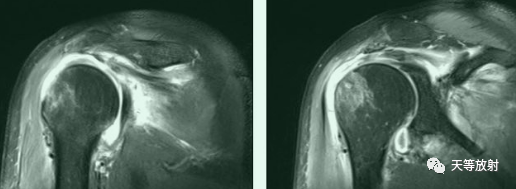

冈上下肌撕裂